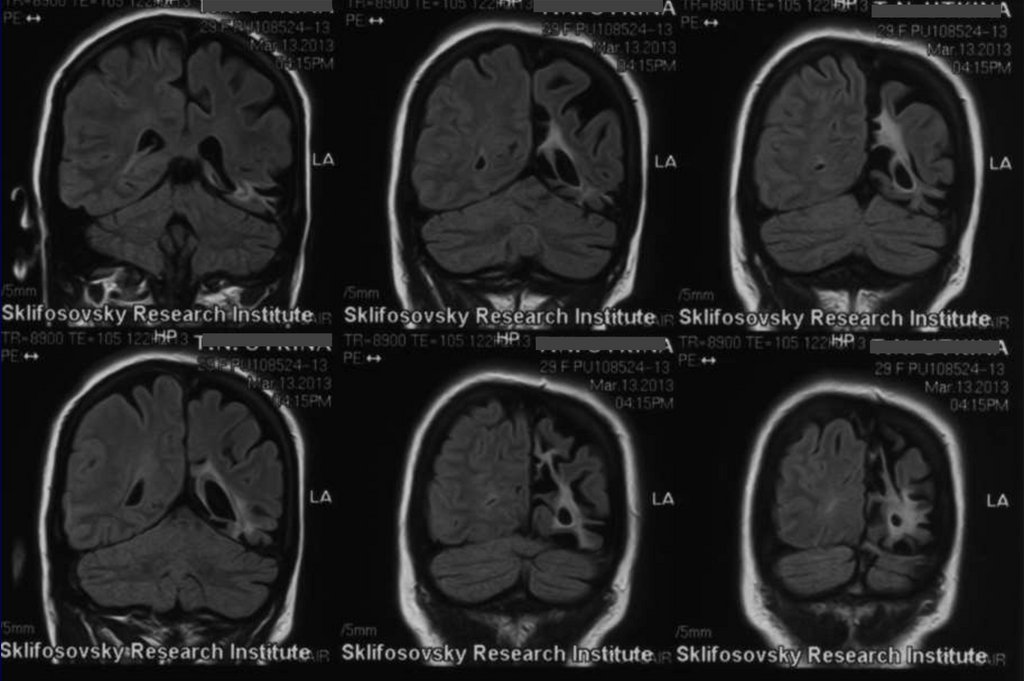

44. Аппаратные методы исследования:

• МРТ от 13.03.2013 – глиозно-кистозные

изменения преимущественно в левой

45. МРТ от 03.2013